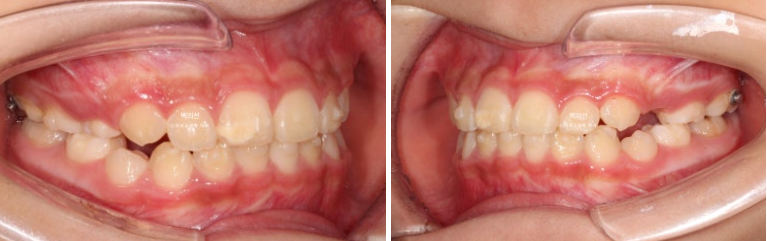

23.12~25.03

치아중심선은 잘 맞고

앞니 배열도 좋습니다.

입매도 잘 유지가 되었고